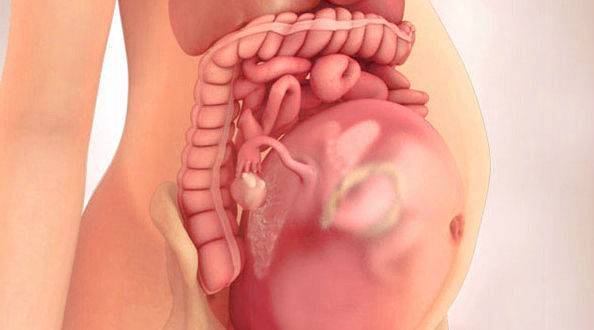

Тошнота на 37 неделе беременности: причины и рекомендации